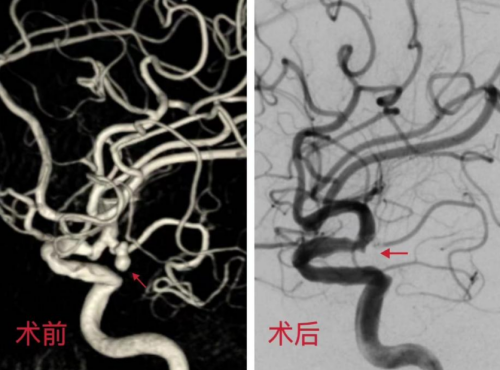

幸运的是,江津自发病后没有放弃查明头痛原因,及时就医,赢得了对症治疗的机会。根据患者的病情发展,徐伟提出施行左侧后交通动脉瘤支架辅助下弹簧圈栓塞手术的介入治疗方案,这是一种微创治疗方法,通过在动脉瘤内放置金属线圈来阻断血流,促使瘤体血栓形成,从而防止未来再次破裂的风险。与传统的开颅手术相比,这种介入栓塞治疗方法具有创伤小、恢复快等优势。

完善术前准备后,经过2个小时的介入手术,患者颅内这颗“不定时炸弹”被成功拆除,解除了再次破裂的风险。目前,患者病情稳定,正在逐步康复中。